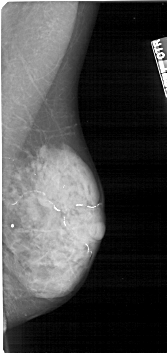

A_1223_1.LEFT_CC

FILE: A_1223_1.LEFT_CC.OVERLAY

TOTAL_ABNORMALITIES 1

ABNORMALITY 1

LESION_TYPE CALCIFICATION TYPE PLEOMORPHIC DISTRIBUTION CLUSTERED

ASSESSMENT 4

SUBTLETY 4

PATHOLOGY MALIGNANT

TOTAL_OUTLINES 1

BOUNDARY